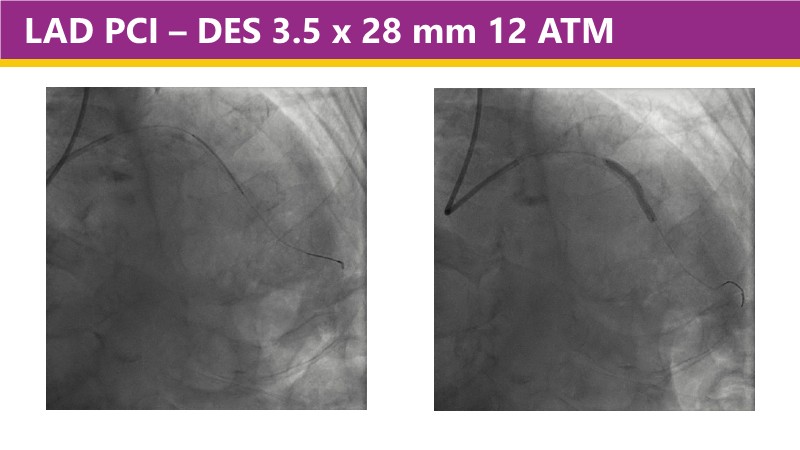

This EuroPCR 2025 session shares real-world insights confirming the promising results of the PINNACLE I trial, with LithiX IVL proving safe and effective across eccentric, concentric, and nodular calcifications.

Learn how this technology works, review the supporting evidence, and follow step-by-step case examples demonstrating optimal stent expansion and an efficient calcium modification workflow in daily practice.